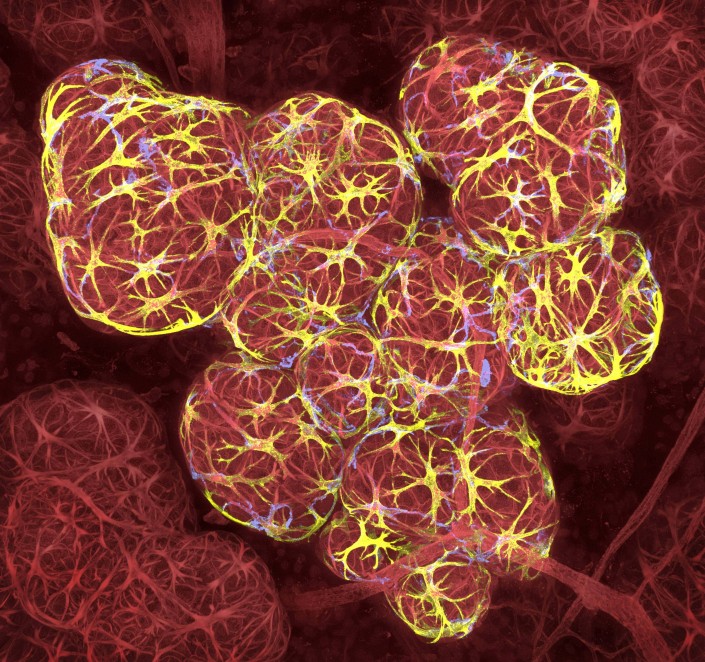

17-е место. Ткань молочной железы в период лактации, 63-кратное увеличение.

Калеб Доусон, Институт медицинских исследований Уолтера и Элизы Холл, Австралия